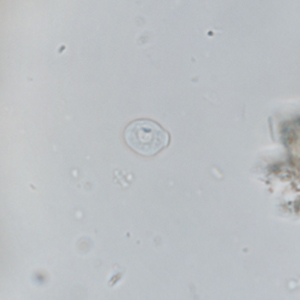

Chilomastix mesnili cysts are small (6 to 10 µm in diameter), pyriform and have a thin and refringent outer membrane. They have a subcentral nucleus and a cytostome containing its flagella. However, this structure is difficult to visualize (Garcia, 2021). Iron hematoxylin staining allows its proper visualization.